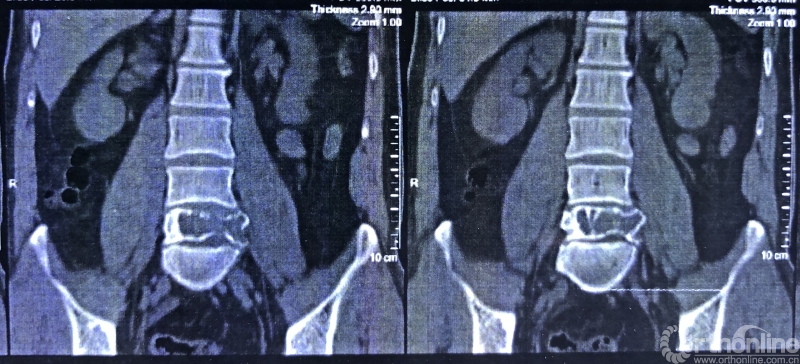

据介绍,患者为39岁男性,在一年前开始出现腰部反复疼痛的症状,休息下后疼痛还可以缓解,当时并未引起患者重视。过年后感觉疼痛加重,赴当地医院检查。核磁共振显示腰椎上长了一个鹅蛋大小的肿瘤,不偏不倚地侵蚀在第五节腰椎上,正是腰椎和骨盆连接部位附近。于是患者来同济医院骨科就诊。

就诊前CT

通过对患者详细的身体检查、穿刺活检和综合评估后,确诊患者是腰椎骨巨细胞瘤,第五腰椎破坏70%以上,邻近软组织也有破坏。这种肿瘤属于交界性的有恶性倾向的良性肿瘤,若不彻底切除,患者疼痛会逐渐加剧,甚至因骨质坍塌而瘫痪,若肿瘤细胞转移更会危及生命。若是能在早期尽快彻底、完全地切除肿瘤及被侵蚀椎体,病人才很可能完全战胜肿瘤。